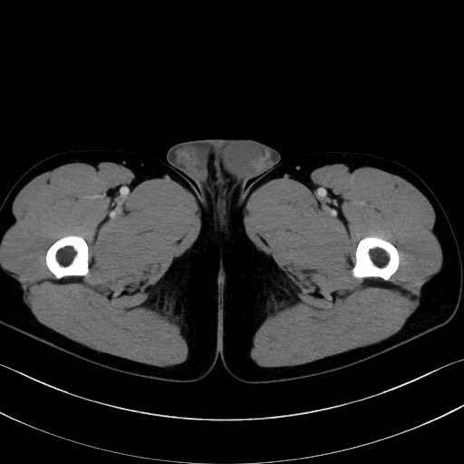

中殿筋 (Gluteus medius)